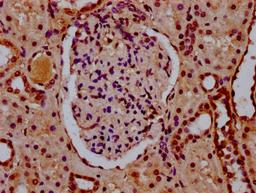

IHC image of CSB-PA010403OA34nsucHU diluted at 1:10 and staining in paraffin-embedded human kidney tissue performed on a Leica BondTM system. After dewaxing and hydration, antigen retrieval was mediated by high pressure in a citrate buffer (pH 6.0). Section was blocked with 10% normal goat serum 30min at RT. Then primary antibody (1% BSA) was incubated at 4°C overnight. The primary is detected by a biotinylated secondary antibody and visualized using an HRP conjugated SP system.